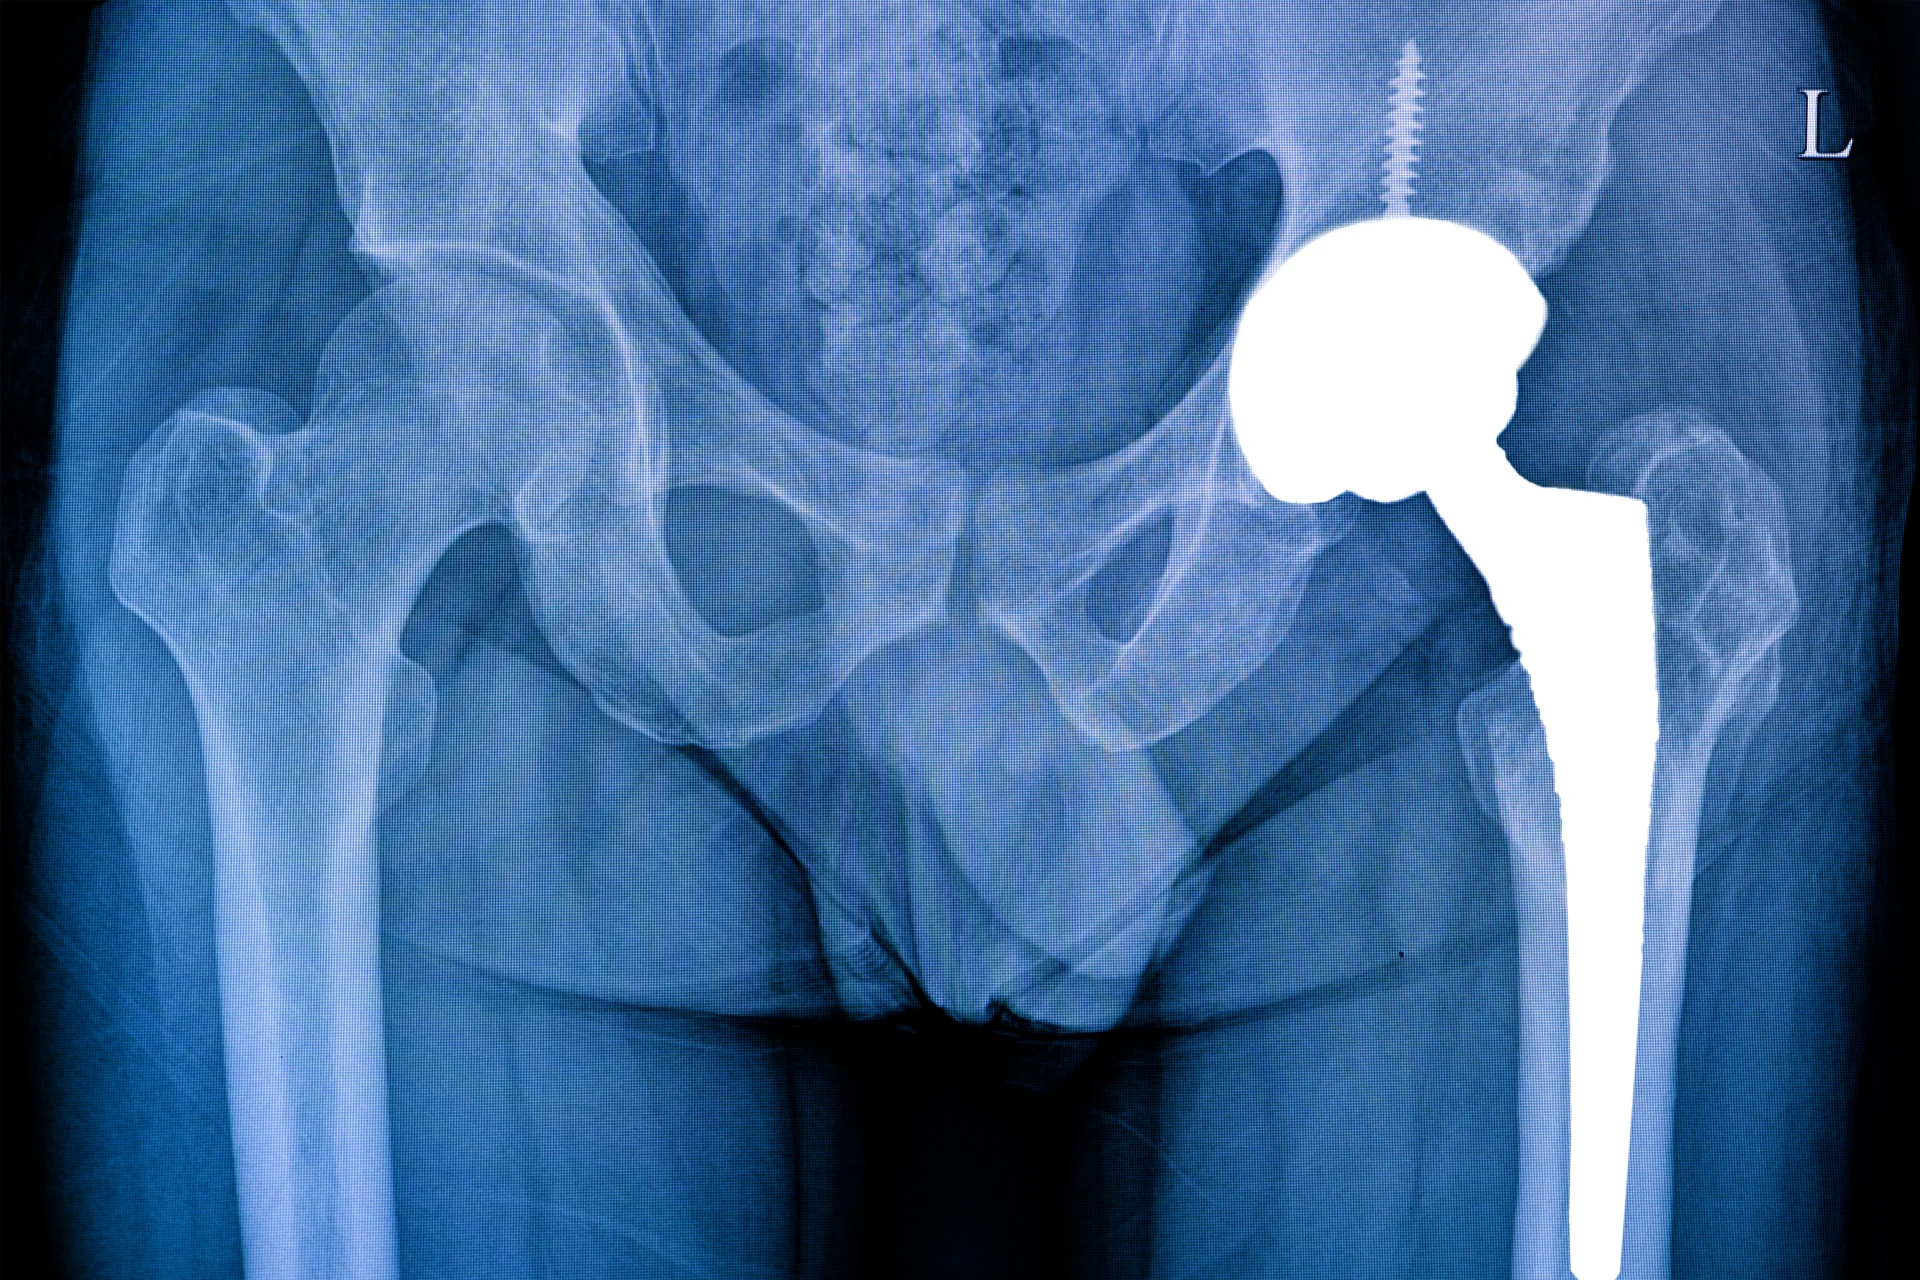

Эндопротезирование тазобедренного сустава – это высокотехнологичная операция. Во время выполнения этого вмешательства происходит полная или частичная замена тазобедренного сустава прочным имплантатом, другое его название – искусственный эндопротез. Это позволяет полностью восстановить нарушенные ранее функции сустава и ставит на ноги тех, кто еще совсем недавно не мог самостоятельно передвигаться. Цена операции зависит от выбранной методики лечения и эндопротеза.

Эндопротезирование встречается частичное – заменяют только суставной элемент и тотальное – заменяют весь сустав целиком. После введения препарата для анестезии хирург делает разрезы для доступа к пораженному суставу, при этом окружающие структуры не повреждаются. Далее происходит удаление части или всего сустава.

На место удаленного тазобедренного сустава устанавливается эндопротез, после чего проверяется функция конечности и операционная рана послойно ушивается и дренируется определенный период времени. Всего для замены тазобедренного сустава может потребоваться от полутора до трех часов в зависимости от сложности.